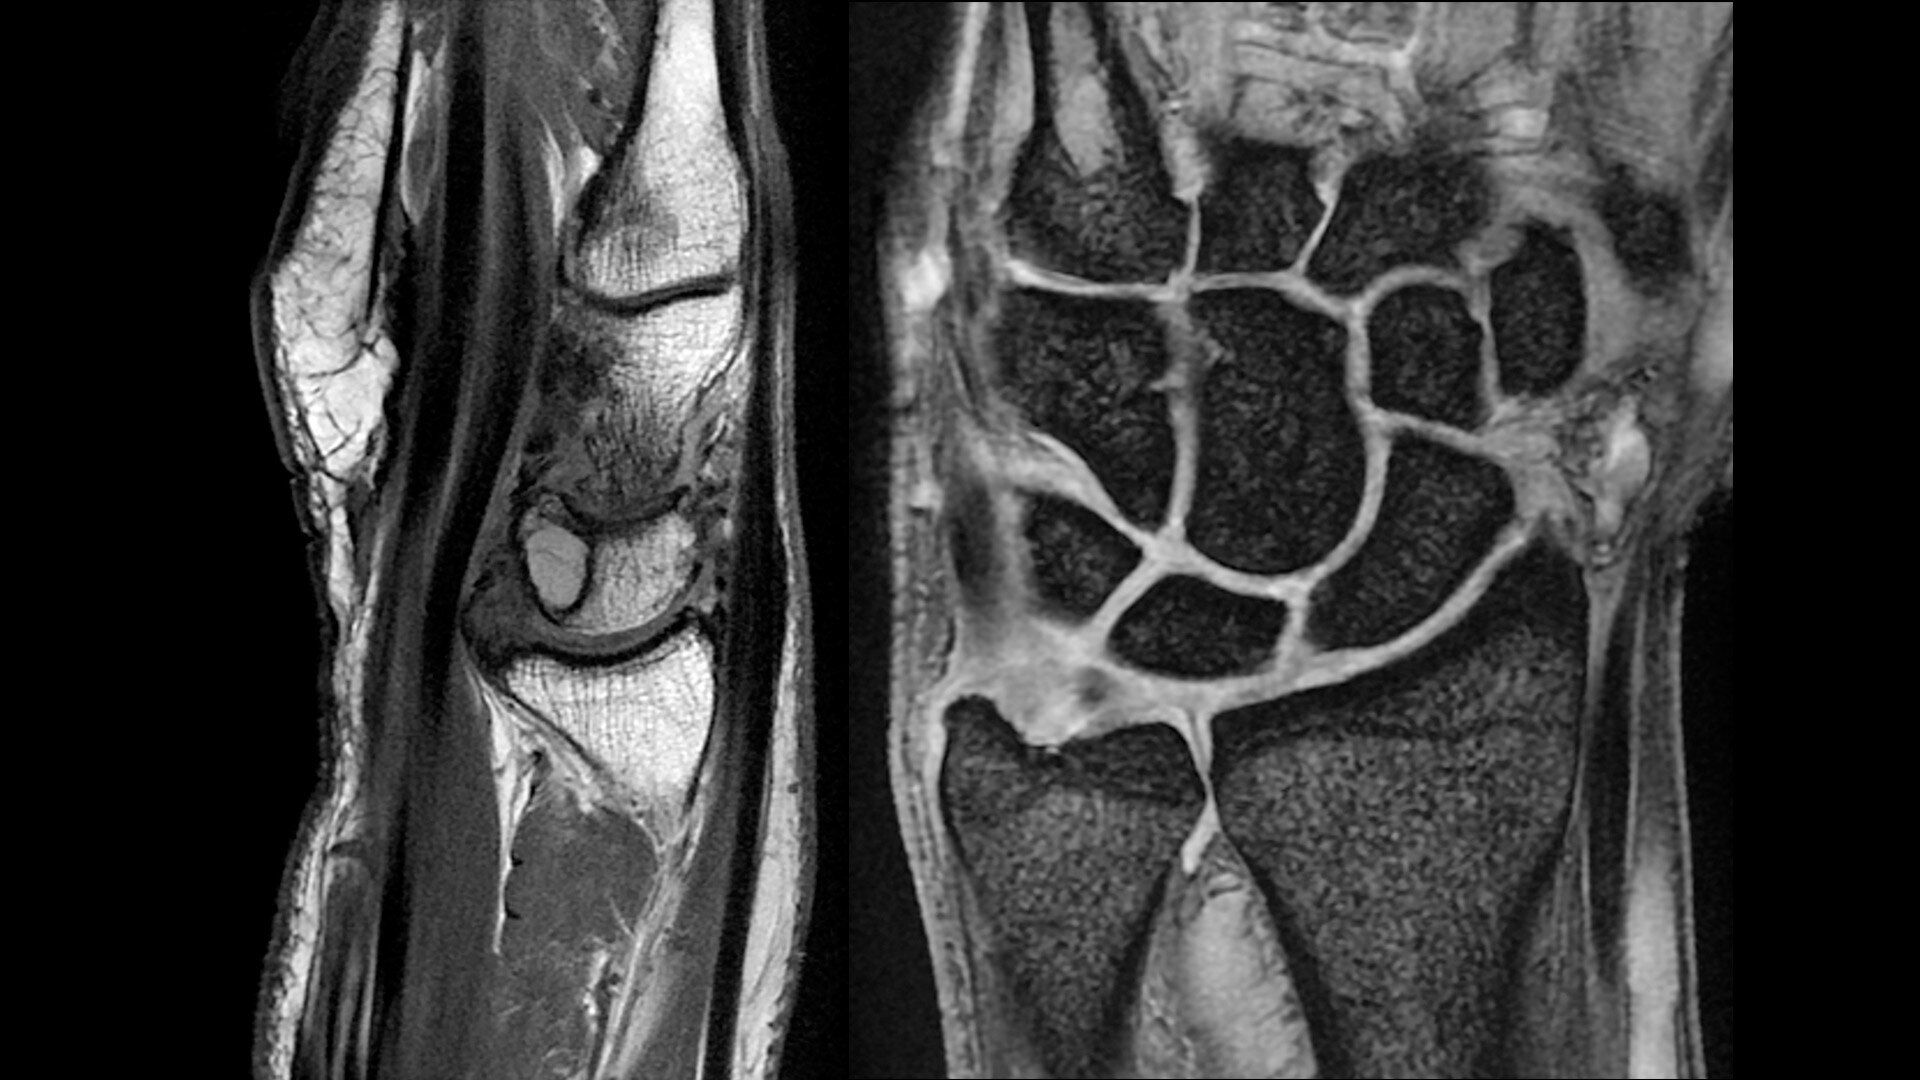

The shape of the MRI coil no longer determines what you can do with it. Wrap it around a knee for a complete knee image. Drape it over the patient's body. With an adaptive AIR™ Coil that is light, form fitting and easy to position, it’s the closest you can get to total positioning freedom with 360-degree coverage.

• 360 degrees of coverage for MSK imaging

• 38% lighter per channel compared to previous generations of conventional coil technology

• Increased acceleration compared to previous generations of conventional coil technology

• Positioning freedom with previously hard-to-scan anatomies

• 20-ch and 21-ch design to accommodate all patient sizes and anatomies